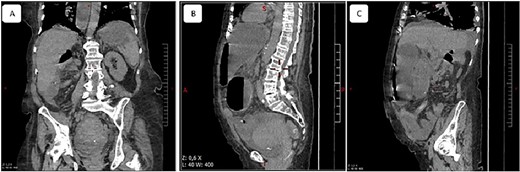

A 65-year-old woman presented to the emergency department with a complaint of acute abdominal pain and distention accompanied by nausea, vomiting and constipation of 2 days. She had a history of diabetes, hypothyroidism, dyslipidemia, mixed connective tissue disease and cholecystectomy. On examination, she had signs of septic shock with a hemodynamic instability, a Glasgow coma scale of 13 with generalized abdominal defense. Initial blood count showed elevated white blood cells (WBC) 22 000 elem/mm3 and C-reactive protein (CRP) of 500 mg/l and procalcitonin of 96 ng/ml. Her lactate on venous blood gas sampling doubled within an hour from 1.64 to 2.3 mmol/l. An urgent abdominal computed tomography (CT) was performed and revealed a dilated loop of bowel within the left upper quadrant and the lesser sac through the foramen of Winslow (Fig. 1). Furthermore, peritoneal fluid and some air bubbles related to intestinal perforation were observed in the omental bursa (Fig. 2). There was also mass effect on the hepatic hilum anteriorly and the inferior vena cava posteriorly. The stomach was pushed back antero-laterally with stretched mesenteric vessels directed to a central point (Fig. 3).

Multiple planes of computed tomography depicting the herniated cecum within the lesser sac. Reconstructed images: (A) axial, (B) and (C) sagittal views.